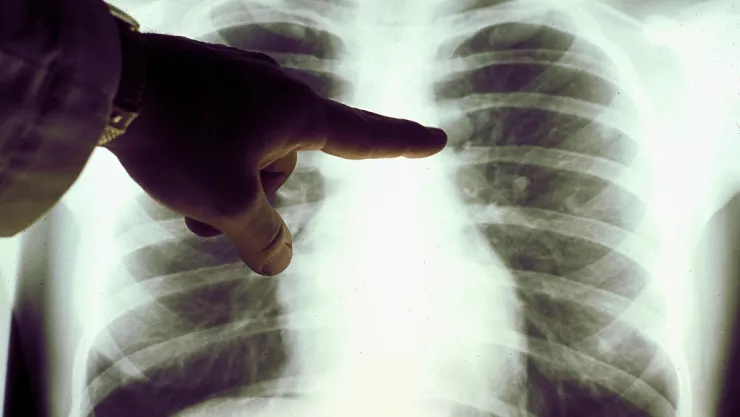

Una simple prueba de orina podría detectar de forma temprana la presencia de cáncer de pulmón, de acuerdo con una investigación publicada en la revista médica Science Translational Medicine.

La prueba, explicaron, está basada en nanopartículas (que se pueden inyectar o inhalar), las cuales, en función con proteínas relacionadas con dicha enfermedad, liberan biomarcadores que luego se pueden detectar en una prueba de orina.

Para probar la nueva herramienta, los científicos utilizaron los sensores en modelos de ratones con cáncer de pulmón. Descubrieron que se podían detectar los tumores con precisión en los animales desde las 7.5 semanas, cuando las neoplasias tenían apenas 2.8 milímetros cúbicos.

Además, apuntaron, la prueba pudo distinguir entre el cáncer en etapa inicial y la inflamación no cancerosa de los pulmones.